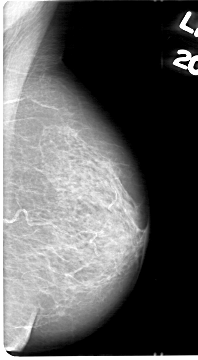

D_4044_1.LEFT_CC

LEFT_CC LINES 5101 PIXELS_PER_LINE 2731 BITS_PER_PIXEL 12 RESOLUTION 43.5 NON_OVERLAY